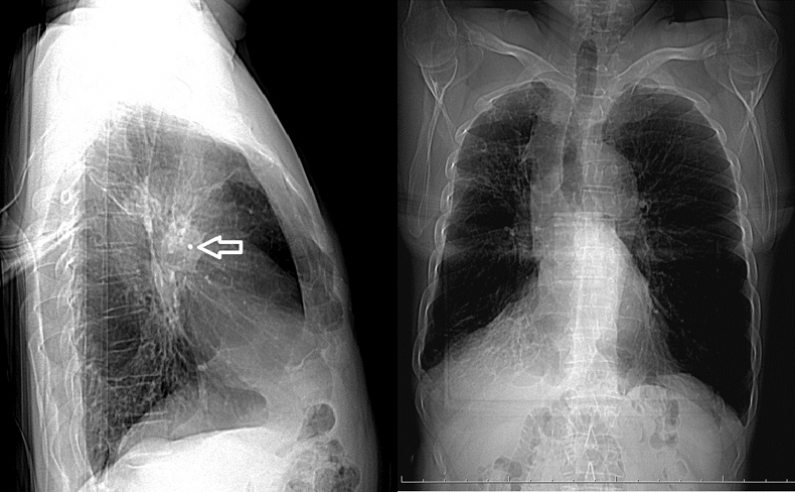

Рентгенограмма органов грудной клетки — плоскостное изображение трехмерного объекта, а значит, имеет «немые зоны», которые не могут быть оценены. Например, большая часть нижней доли левого легкого спрятана за тенью сердца. Поэтому стандартную обзорную рентгенографию делают минимум в 2 проекциях: прямой (задне-передней, для предохранения молочных желез от повышенного облучения) и боковой (обычно левой). Правая боковая или косые проекции — по решению рентгенолога для уточнения или подтверждения патологических изменений в легких. Рентген не отображает очаги меньше 2 мм. Эффективная эквивалентная доза в прямой проекции — 0,18 мЗв, в боковой — 0,24 мЗв.

Часто рентген не позволяет достоверно отличить, скажем, осумкованный плевральный выпот по междолевой щели от ателектаза легкого, если последнее не уменьшено. Деструкция в инфильтрации, не всегда видимая на снимках, может присутствовать или быть суммой слившихся между собой инфильтратов.

Рентгенограммы не сохранились. Судя по КТ-топограммам, в прямой проекции подозрений на инородное тело в бронхе не возникало из-за суммации теней, а вот в боковой его можно было бы предположить на основании достаточно четких круглых контуров. Но пациенту снимки делали только в прямых проекциях, а боковыми пренебрегали.